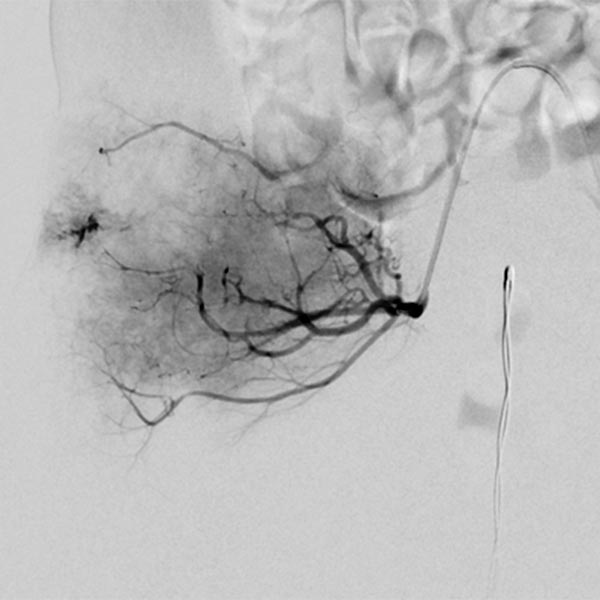

The tumor shows the typical tumor blush with diffuse, strong contrast enhancement on DSA after super-selective catheterization with the microcatheter.

Via the microcatheter, the tumor is now gradually embolized super-selectively with particles 150 microns in size via the supplying arterial branches.

In the control DSA, the main part of the tumor has now been successfully embolized and cut off from the circulation. Only very cranial tumor-supplying branches remained at this stage of the embolization.

These very cranial parts are now also catheterized super-selectively with the microcatheter and embolized with particles. For better navigation of the microcatheter, the vessels from a previous injection are electronically overlaid by the computer (so-called “overlay display”, white in the image).